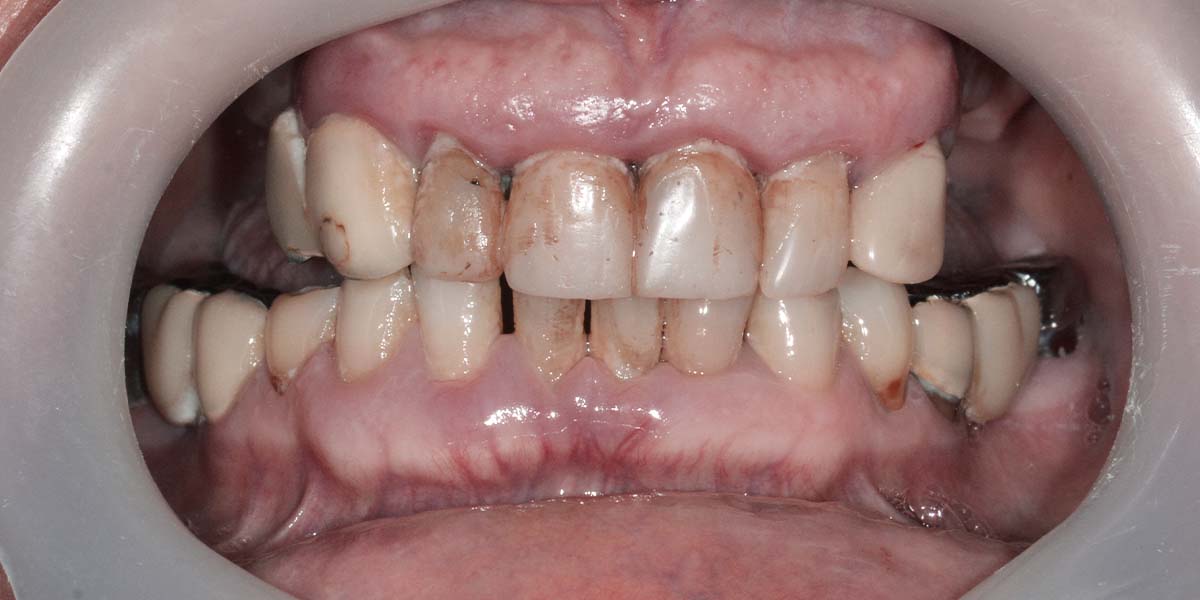

Ponia – charizmatiška ir aktyviai bendruomenės veikloje dalyvaujanti moteris, kuriai gyvenimo džiaugsmą teikia galimybė bendrauti su kitais žmonėmis. Vis tik ilgainiui bendravimo malonumą temdyti pradėjo dantų trūkumas ponios Elenos burnoje.

Moteris ryžosi pokyčiams ir į „PAPADENT“ kliniką atvyko planinei implantacijai. Tuo metu jos burnoje tebuvo likę vos keli dantys, kurie operacijos metu pašalinti ir įsriegti 5 implantai, uždėtas laikinas „All-on-4“ protezas.

Pacientė atvyko į „PAPADENT“ odontologijos kliniką Vilniuje dėl planinės dantų implantacijos. Burnoje likę tik keli dantys, kurie dėl jų būklės buvo pašalinti per procedūrą. Atlikus šią operaciją, buvo įsriegti penki implantai, o laikinai uždėtas „All-on-4“ protezas. Po gijimo laikotarpio, pacientė nusprendė pasirinkti nuolatinį viso žandikaulio protezą (dantų protezavimo kainos Vilniuje), pagamintą iš metalo ir akrilo, ant penkių implantų.